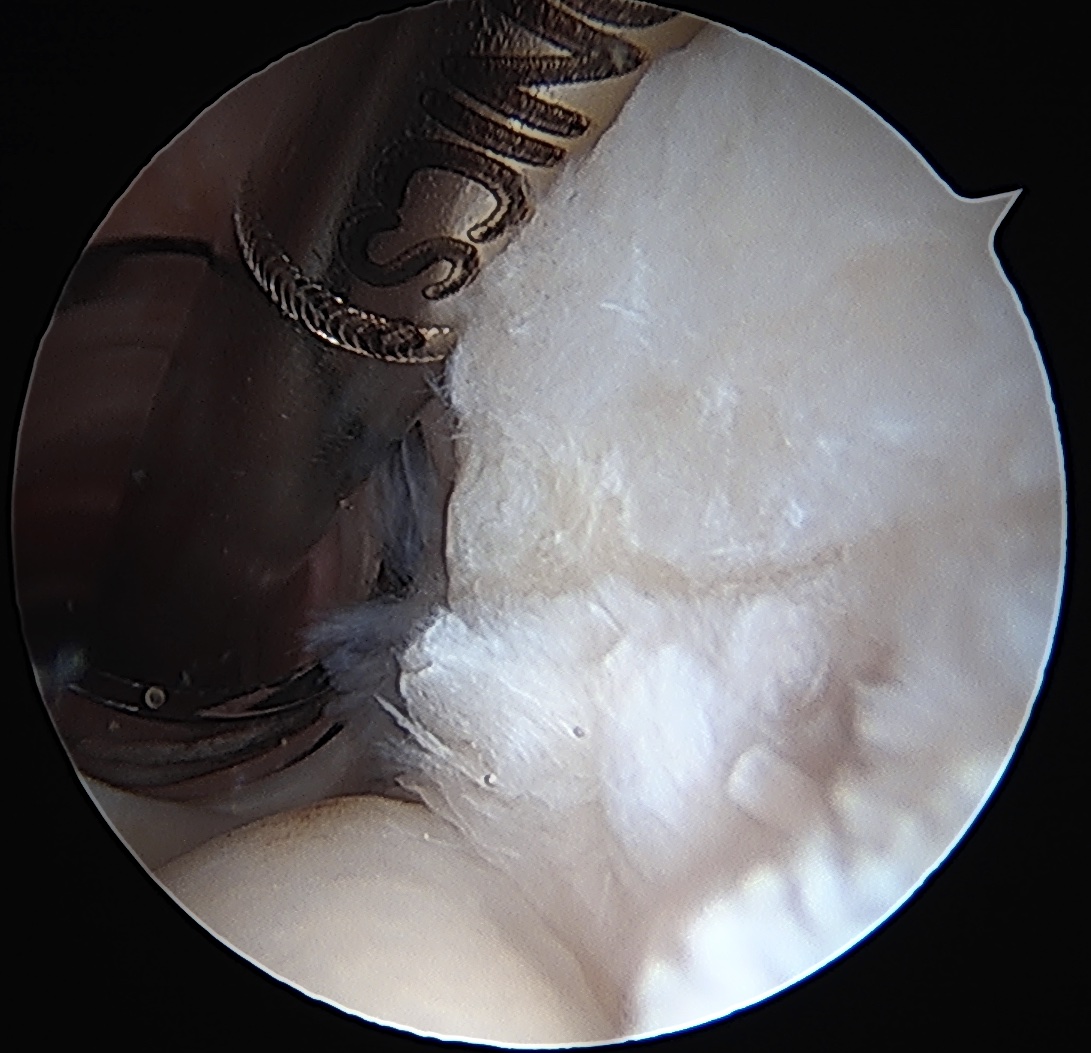

Tear completion and repair

Articular sided tear / PASTA

Technique

Camera in glenohumeral joint

- use spinal needle to identify center of PASTA

- pass 1 PDS to mark lesion

- camera into subacromial space

- use suture to identify area for tear completion

- cautery or knife to complete tear

- double row repair